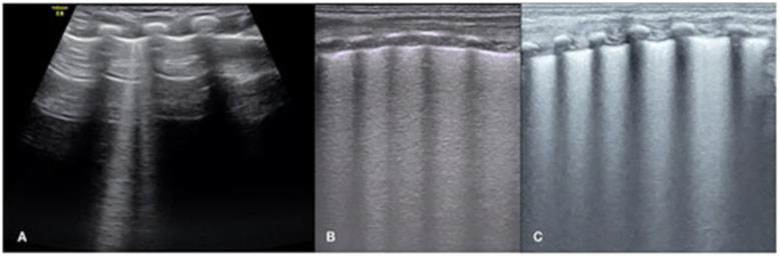

- Рекомендуется новорожденному ребенку с дыхательными нарушениями селективное проведение ультразвукового исследования легких для выявления признаков РДС при наличии возможностей медицинской организации [57 - 59].

Уровень убедительности рекомендаций C (уровень достоверности доказательств - 5).

Комментарий: см. Приложение Г3. Оценка состояния паренхимы по ультразвуковой шкале легких LUS или eLUS.

Данная шкала позволяет:

- дифференцировать респираторный дистресс-синдром (РДС) и транзиторное тахипноэ новорожденных (ТТН). РДС характеризуется плохо аэрируемым легким с отсутствием A-линий, наличием небольших "субплевральных" консолидаций и диффузным белым легким (сливающиеся B-линии). Напротив, при ТТН интерстициальный рисунок чередуется с областями почти нормального легкого (с A-линиями) [57].

- оценить степень тяжести РДС [59 - 61];

- уточнить показания для введения экзогенного сурфактанта [62];

- оценить риски развития БЛД.